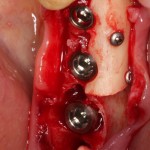

Делаем анестезию, разрез, скелетируем костную ткань:

На фотографиях хорошо видны оставшиеся после удаления объемы костной ткани. Давайте рассмотрим плюсы и минусы текущей клинической ситуации, применительно к нашему плану:

Итак, позиционируем имплантат. Для начала, с помощью пина:

Лунка готова, устанавливаем имплантат:

Продолжим нашу работу. Имплантат установлен: